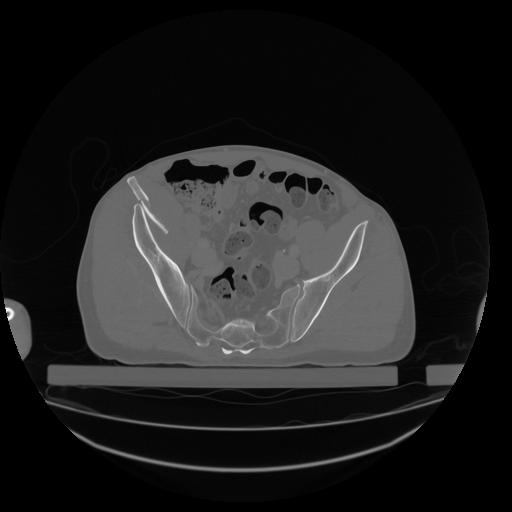

34 CUERPO,CE,Vol,1.0,CUERPO,,